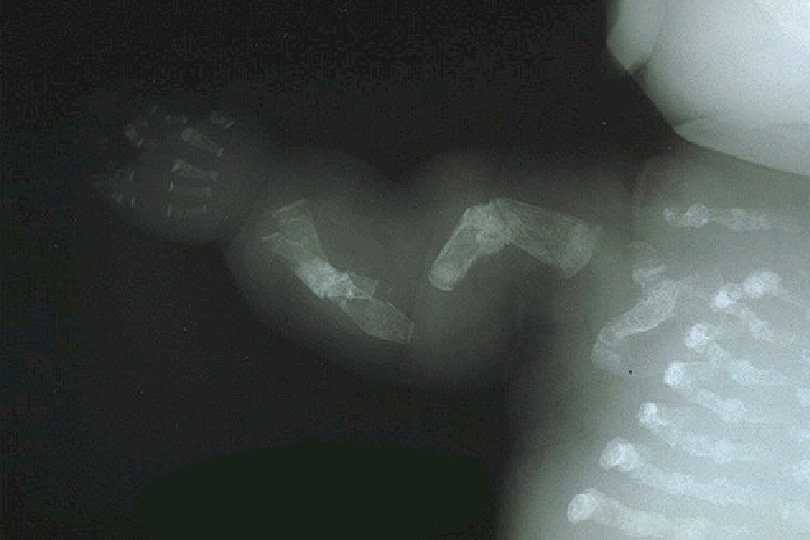

9. Membros MEMBROS SUPERIORES E INFERIORES • comprimento total • proporção entre braço/antebraço e coxa/perna • fraturas MÃO e PÉ • medidas • dedos

MEMBROS SUPERIORES E INFERIORES Hipoplasia Femoral Artrogripose Múltipla